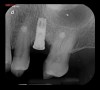

The first step in preventive strategies must be to perform a correct diagnosis of the peri-implant condition by accurately assessing the health of the peri-implant hard and soft tissues through periodontal probing and periapical radiographs at the time of definitive prosthetic installation. These measurements should be considered the baseline diagnosis and, therefore, represent a true starting point for evaluating the changes on the radiographic bone levels and probing pocket depths (PPD) at future recall appointments (Figure 1 and Figure 2).6 Although probing depth measurements of peri-implant tissues do not have the same diagnostic value as probing periodontal tissues, there is evidence that BOP is the most objective sign of peri-implant tissue inflammation; significant deepening of PPD compared with baseline measurements is also a sign of disease that indicates the need to perform a radiographic evaluation (Figure 3 through Figure 5).6,10,11

Fig 1. Baseline measurements at the time of prosthetic delivery: probing pocket depth and

Figure 1

Fig 2. periapical radiographs.

Figure 2